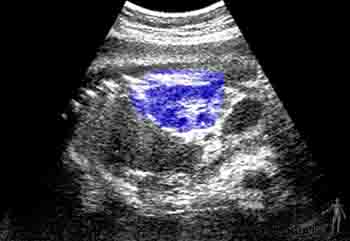

• Quinta semana. Se observa un desarrollo notable del encéfalo. La cara del embrión toma contacto con la prominencia cardíaca. El segundo arco visceral crece formando el opérculo, y cubre a los arcos más caudales, formándose una depresión ectodérmica llamada seno cervical. Ecográficamente a esta edad es posible visualizar el saco gestacional, como una imagen quística más o menos esférica.

• Sexta semana. En los miembros superiores se identifican las regiones del codo y la muñeca y las placas de las manos. En la cabeza, en relación con la primera hendidura faríngea, comienza a formarse el pabellón auricular. Ecográficamente a esta edad es posible visualizar en el interior del saco gestacional al embrión, como una pequeña zona ecorefringente.

• Séptima semana. El intestino en desarrollo se proyecta en el cordón umbilical, formando la hernia umbilical fisiológica. En las manos se observa los rayos digitales que van delimitando a los dedos. Ecográficamente a esta edad el saco gestacional aparece de mayor tamaño y en su interior se aprecia claramente al embrión; también es posible advertir, en la ecografías de tiempo real, sus movimientos cardíacos.

• Octava semana. Se distinguen los dedos de manos y pies y la cola ha involucionado. El embrión ha adquirido características morfológicas humanas. La cabeza representa la mitad de la longitud del embrión y los párpados se desarrollan y se fusionan hacia el final de ésta semana. Ecográficamente a esta edad se aprecia en el interior del saco gestacional el embrión y el saco vitelino. Además se observan los esbozos de los miembros superiores e inferiores y se pueden visualizar los movimientos bruscos del embrión.